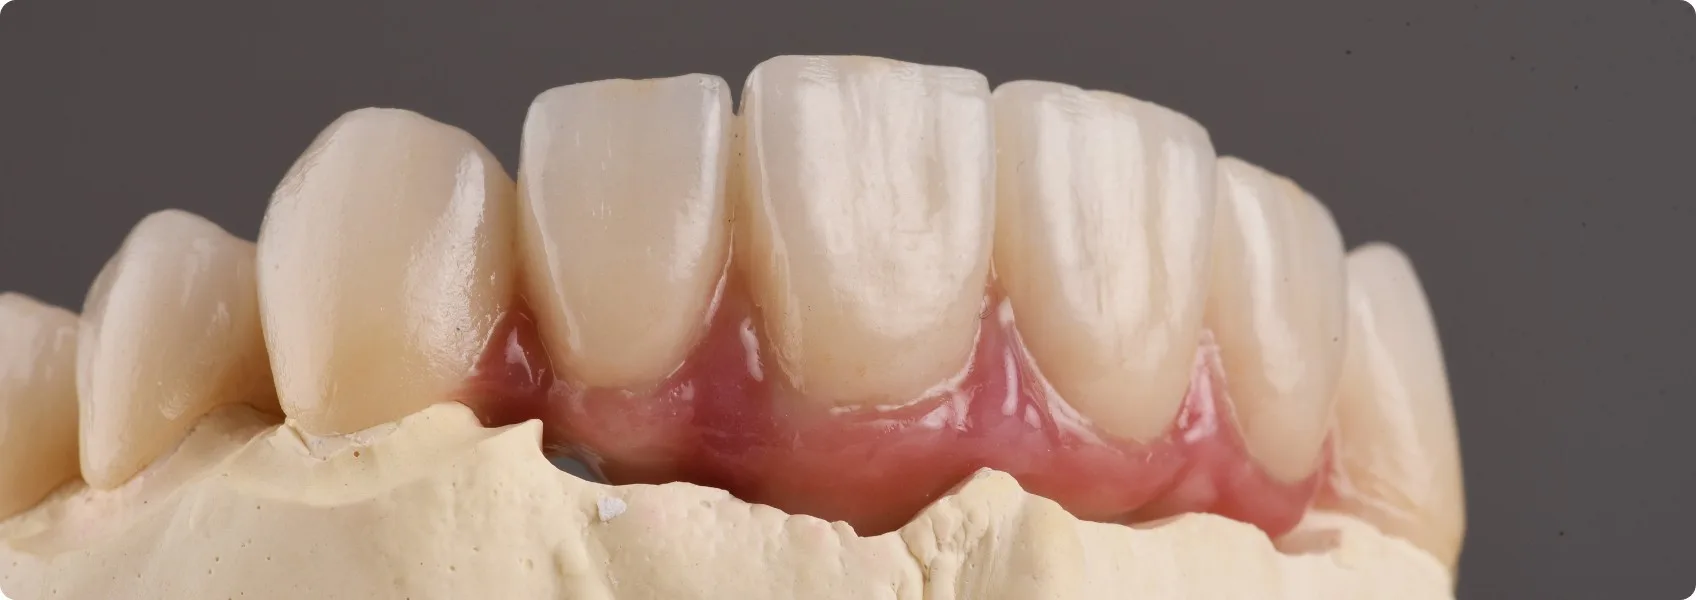

Gdy brakuje dziąsła, nie wydłużamy zębów! To często brzydkie i ryzykowne rozwiązanie, stosowane przez lekarzy, którzy nie chcą lub nie potrafią odtworzyć dziąsła. W NDC nie boimy się masek dziąsłowych — jesteśmy w nich eskspertami.

Nowy uśmiech naszego Pacjenta zrekonstruowaliśmy przy pomocy mostu protetycznego, zamontowanego na jego własnych, wcześniej wyleczonych zębach. Jednak w tym przypadku, aby osiągnąć prawdziwie naturalny i harmonijny efekt, doktor Ewa zdecydowała o zastosowaniu dodatkowego elementu — maski dziąsłowej. Co to takiego?

To indywidualnie projektowana część pracy protetycznej, wykonana z materiału idealnie imitującego naturalne dziąsło. Stosujemy ją, gdy Pacjent ma zbyt mało własnej tkanki miękkiej, np. na skutek recesji czy zaniku kości.

Stworzenie pięknej maski dziąsłowej jest trudne. Wymaga bardziej rozbudowanych protokołów leczenia, dużej wiedzy protetyka i wybitnych umiejętności technika dentystycznego. Pozwala jednak perfekcyjnie odtworzyć prawidłowy przebieg linii dziąseł. Bo piękny uśmiech to nie tylko idealnie białe zęby (estetyka biała), ale także zdrowe i proporcjonalne dziąsła (estetyka różowa). Dopiero ich połączenie daje spektakularny efekt leczenia.

Na ostateczny efekt estetyczny i bezpieczeństwo protezy wpływa mnóstwo szczegółów, o których Pacjenci często nawet nie wiedzą. Jednym z nich jest umiejętne ukształtowanie przęsła mostu. To ta część, która zastępuje brakujący ząb i bezpośrednio dotyka dziąseł.

Aby most doskonale kamuflował braki, jego przęsło musi mieć owalny, gładko przechodzący w dziąsło kształt — tak, by nie było widać, że pod spodem nie ma naturalnego zęba.

Dodatkowo, w miejscu styku odbudowy z dziąsłem Pacjenta, materiał protezy musi być biozgodny, czyli dobrze tolerowany przez organizm. Dlatego tam, gdzie przęsło mostu styka się z tkanką, używamy tylko czystego tlenku cyrkonu. Celowo nie pokrywamy go ceramiką.

Polerujemy jego powierzchnię na błysk! Dzięki temu komórki tkanki miękkiej Pacjenta (fibroblasty) mogą do niego swobodnie przylegać, traktując go niemal jak własną tkankę. Dziąsło Pacjenta „przykleja się” do tego biozgodnego materiału, traktując go jak część siebie. W ten sposób minimalizujemy ryzyko powikłań i alergii.